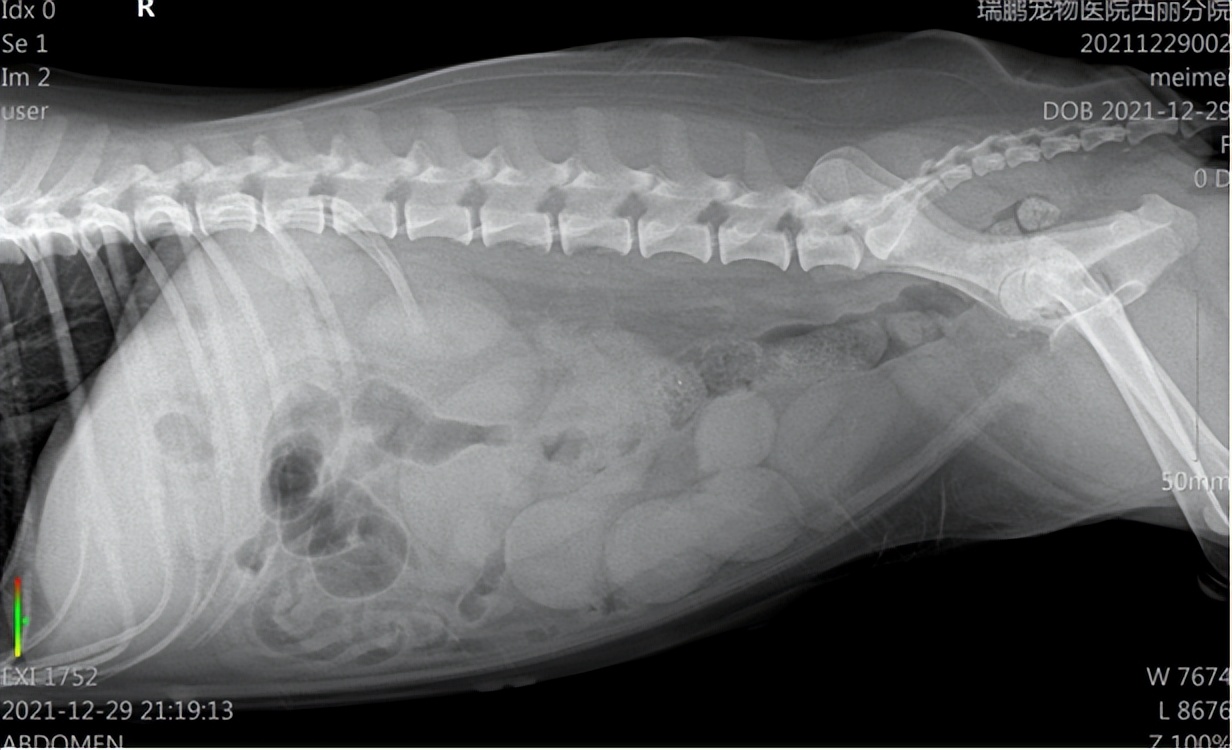

经过进一步血检和影像科检查,发现狗狗体内有炎症,且有子宫体增粗、子宫壁增厚的情况。

根据临床症状和辅助检查,初步诊断狗狗得了子宫蓄脓。

DR检查:发现狗狗子宫体增粗

腹部B超:发现狗狗子宫壁增厚